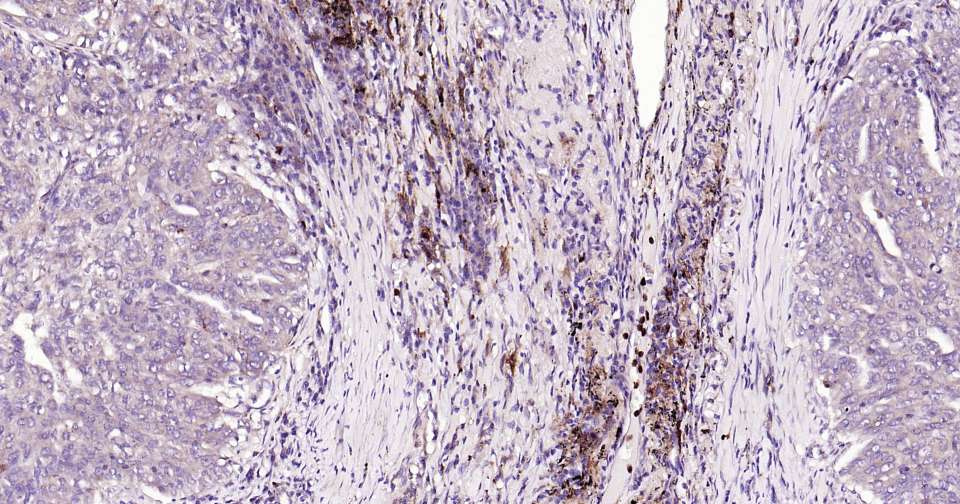

Immunohistochemical analysis of paraffin embedded human lung cancer tissue slide using IHC0311 (MMP9 Kit).

Immunohistochemical analysis of paraffin embedded rat spleen tissue slide using IHC0311 (MMP9 Kit).